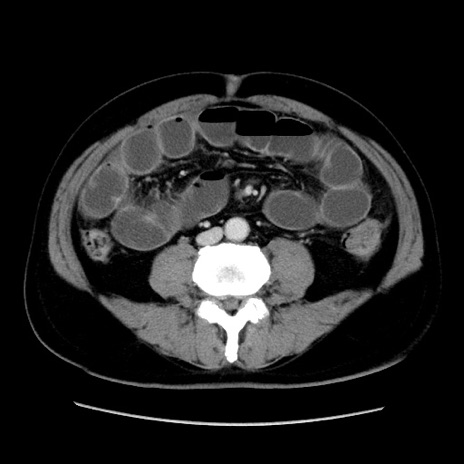

症例16(横断像)

冠状断像